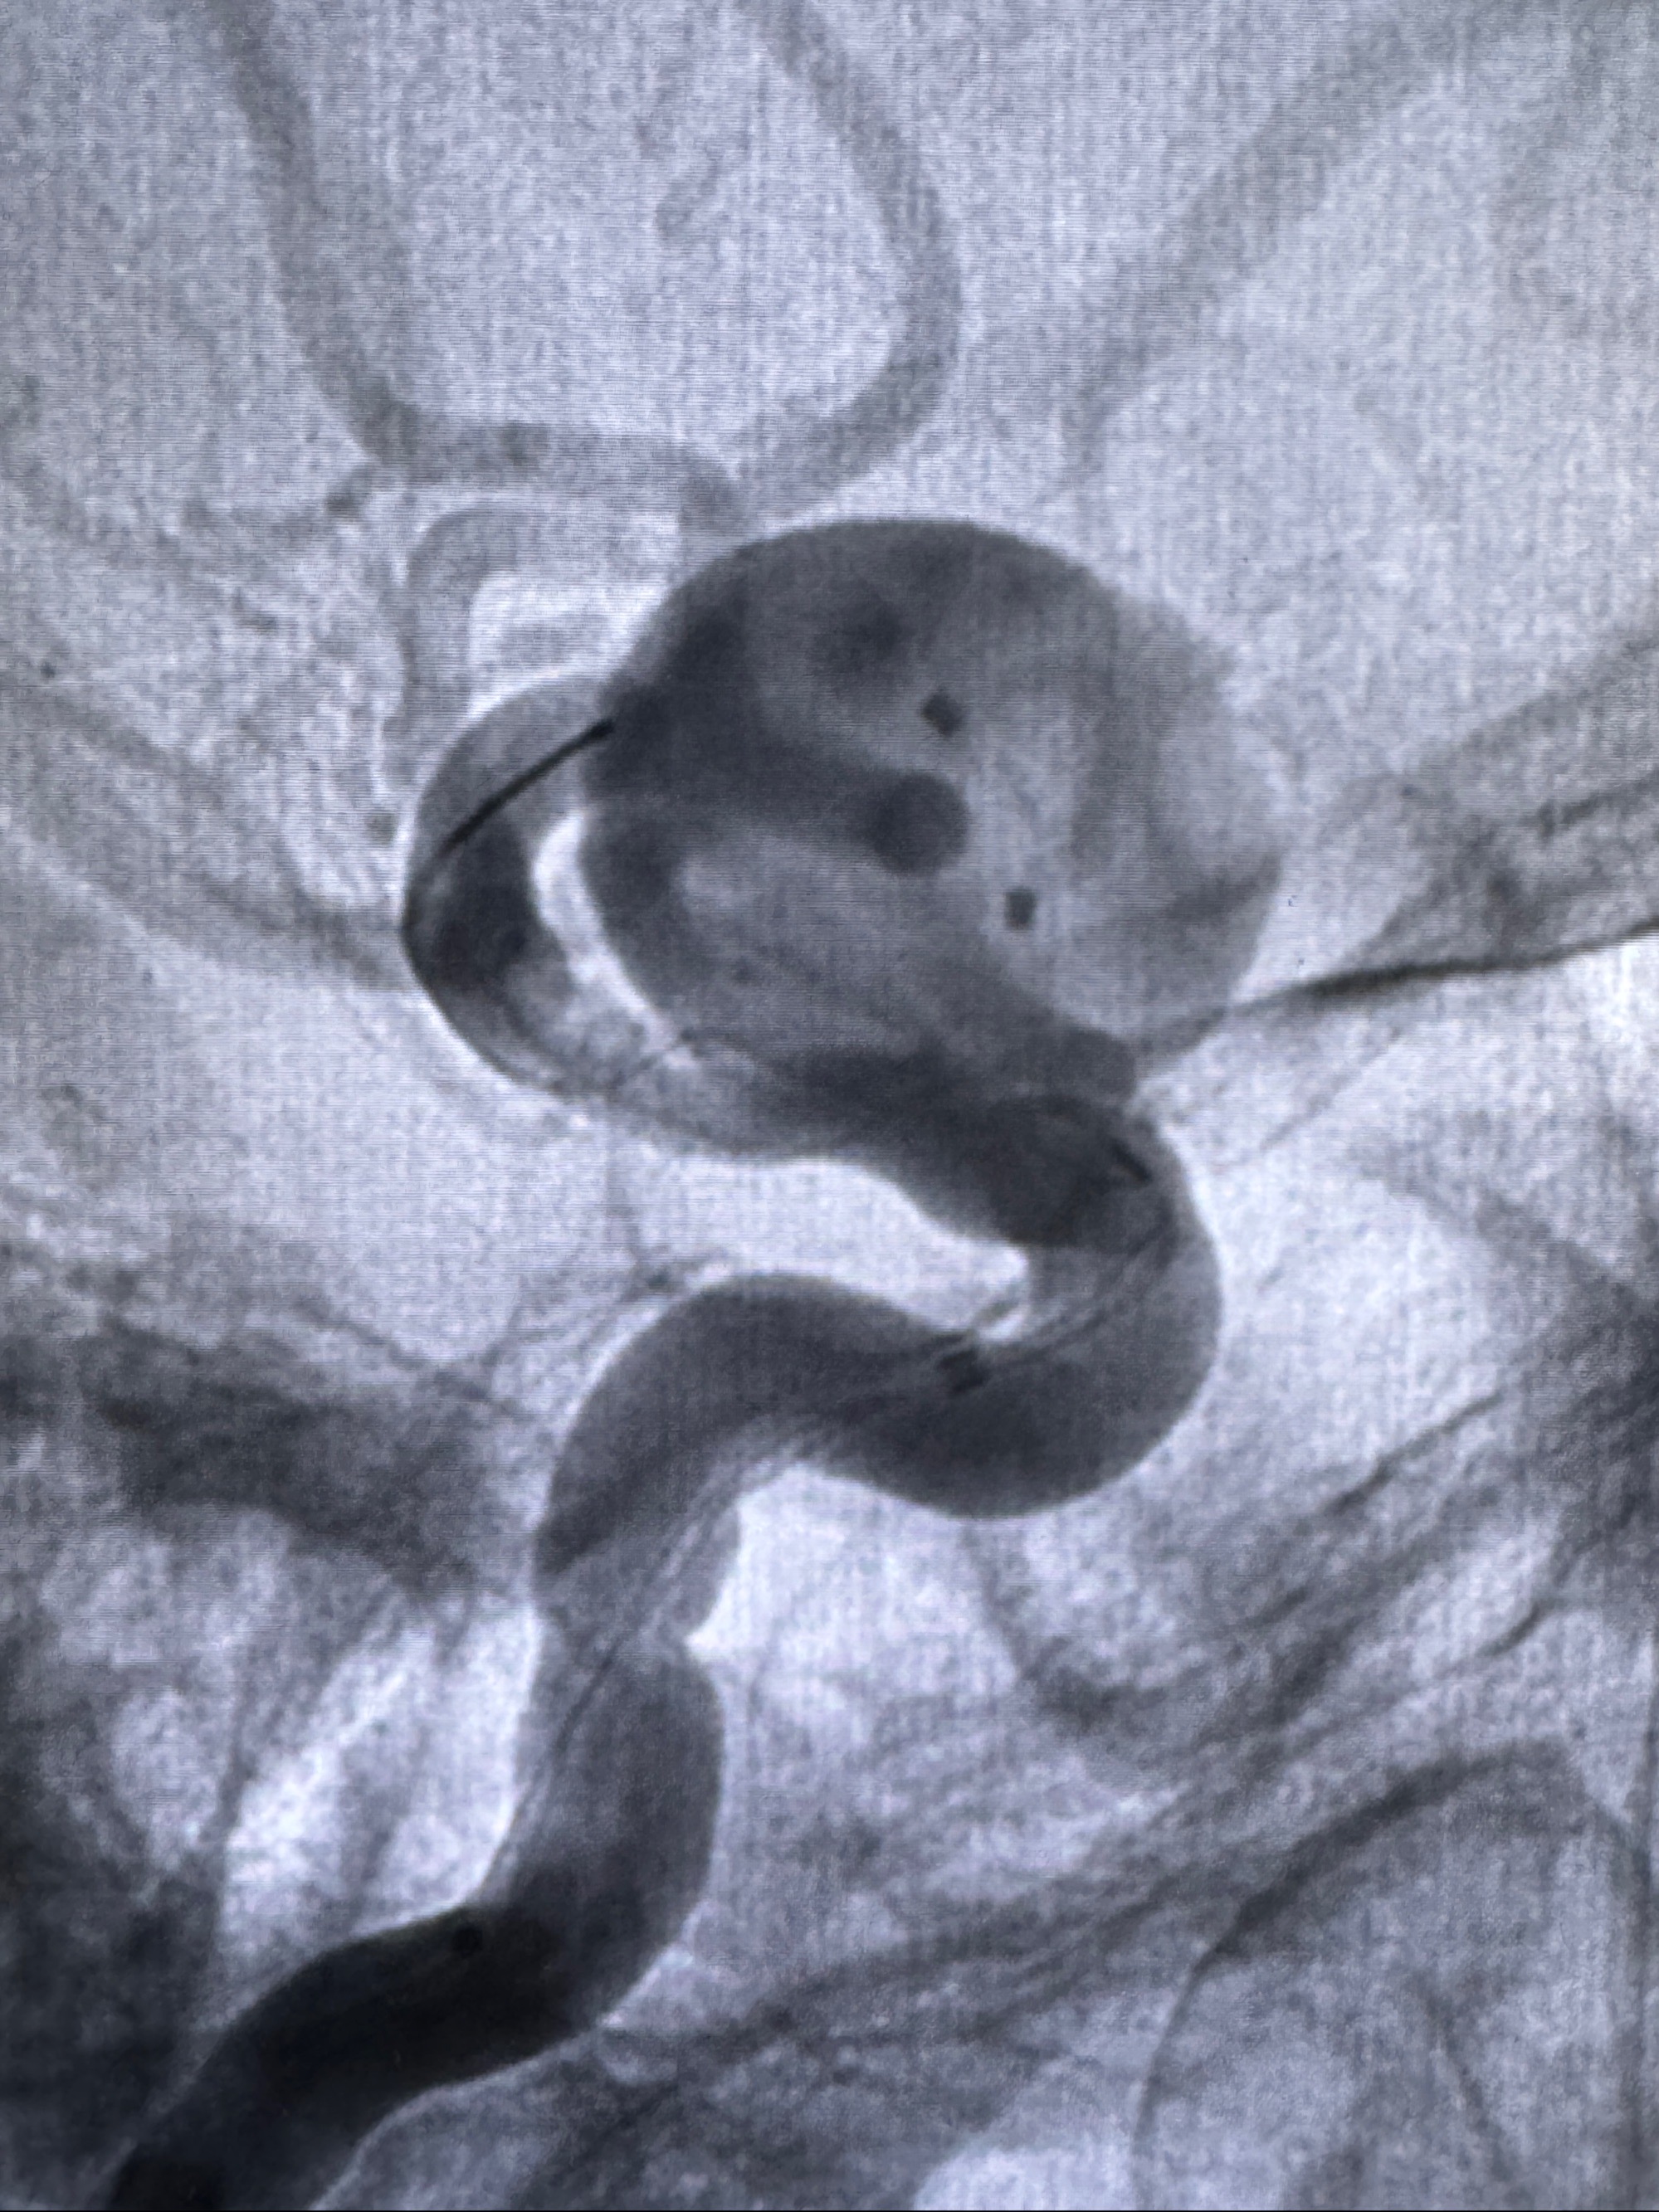

2023-12-08外院DSA:右侧颈眼动脉瘤,约13*12mm大小,压颈试验显示左右向及后向前代偿可

旋转3D展示动脉瘤局部的血管构筑

测量动脉瘤的大小:16*13.8*7.6mm大小,较原先变大,考虑双抗后瘤内血栓溶解可能

观察动脉瘤腔内的血流动力学情况